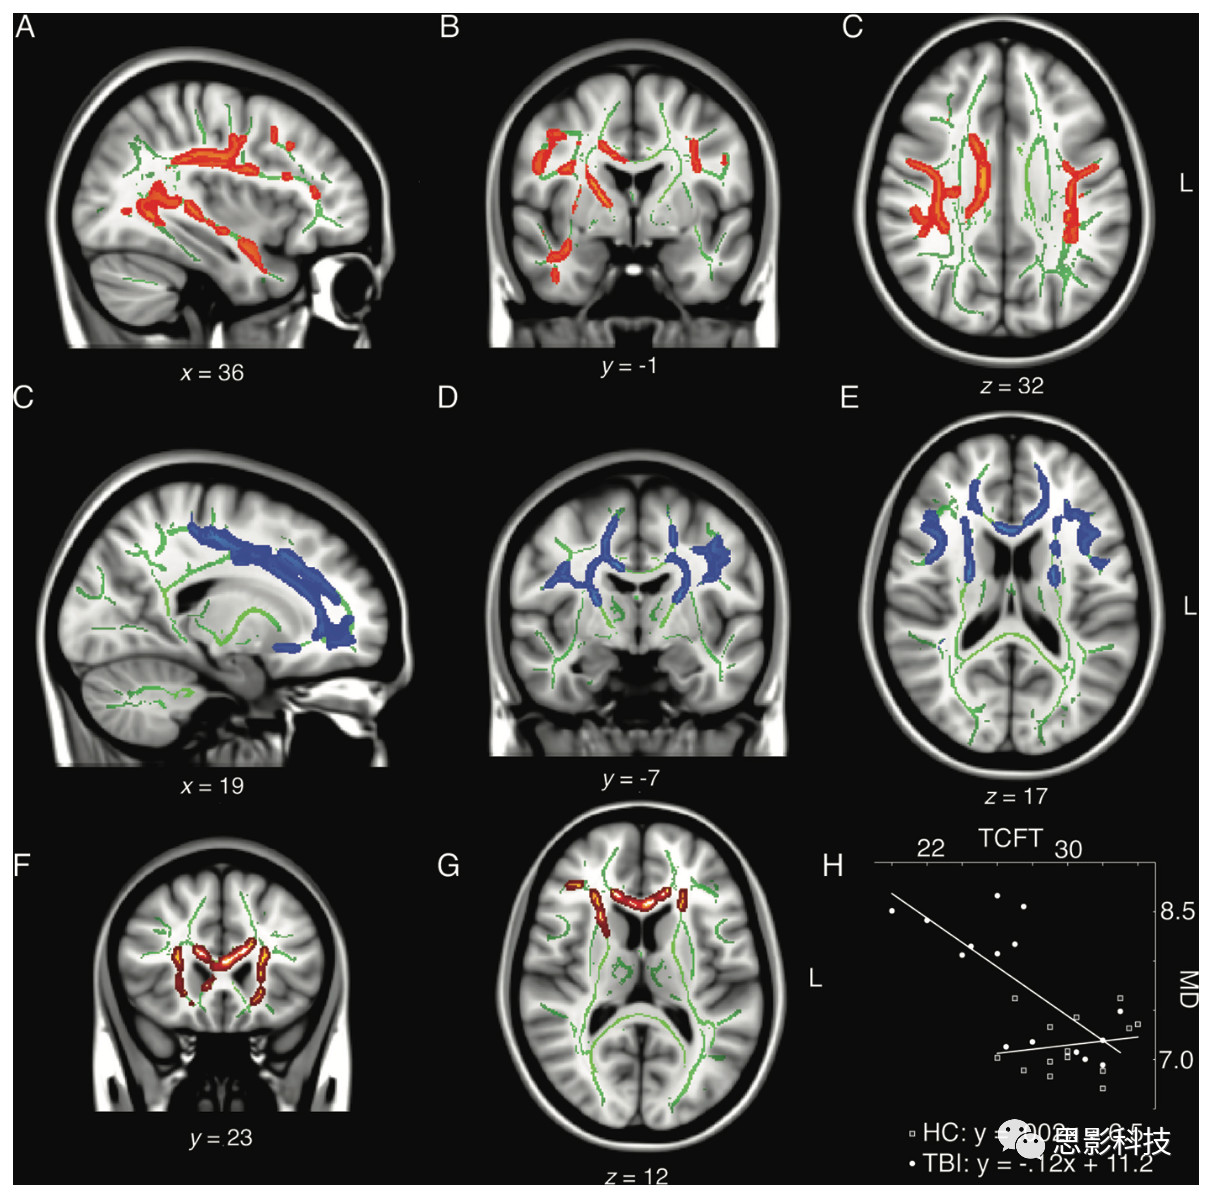

在一項(xiàng)最新的DTI研究中,嘗試控制可能會(huì)對(duì)腦震蕩長(zhǎng)期影響的造成干擾的混雜變量如臨床伴隨疾病或酒精藥物成癮,招募了一批臨床表現(xiàn)正常的退役職業(yè)或半職業(yè)運(yùn)動(dòng)員,對(duì)其進(jìn)行全面的神經(jīng)心理學(xué)測(cè)評(píng)及彌散加權(quán)成像掃描。這批同質(zhì)性樣本中,半數(shù)退役運(yùn)動(dòng)員在職業(yè)生涯中遭受過腦震蕩,退役后并未遭受過腦震蕩(平均傷后時(shí)間37年),且未遭受過與運(yùn)動(dòng)無關(guān)的腦外傷(如車禍傷)。采用TBSS分析發(fā)現(xiàn),遭受過腦震蕩的退役運(yùn)動(dòng)員大腦多個(gè)區(qū)域FA減低及MD、RD增高(圖3)。

3. 早年遭受腦震蕩的老年退役運(yùn)動(dòng)員WM異常(DTI TBSS

A,B,C)經(jīng)歷腦震蕩組與未經(jīng)歷腦震蕩的匹配對(duì)照組相比較FA值減低;

C,D,EMD值增高主要位于額葉白質(zhì);(F,G,H)經(jīng)歷腦震蕩組情景記憶功能下降與MD增高的相關(guān)

根據(jù)動(dòng)物實(shí)驗(yàn)研究,這些異常被認(rèn)為反映了軸索損傷及髓鞘病理改變。從臨床意義上,這些WM完整性與亞臨床認(rèn)知、運(yùn)動(dòng)功能下降存在關(guān)聯(lián)。這些觀察結(jié)果與近期一項(xiàng)通過排除標(biāo)準(zhǔn)嚴(yán)格控制混雜因素的結(jié)果一致。該研究將曾遭受過多次腦震蕩的退役職業(yè)運(yùn)動(dòng)員鉤束、灰質(zhì)異常與行為及認(rèn)知下降進(jìn)行關(guān)聯(lián),并存在相關(guān)。這些發(fā)現(xiàn)提示,早年遭受腦震蕩會(huì)影響隨后數(shù)十年老化的結(jié)構(gòu)及功能衰退。這些結(jié)果提示年輕無癥狀運(yùn)動(dòng)員潛在的WM損傷持續(xù)甚至隨時(shí)間加重,最終導(dǎo)致認(rèn)知、運(yùn)動(dòng)功能下降。